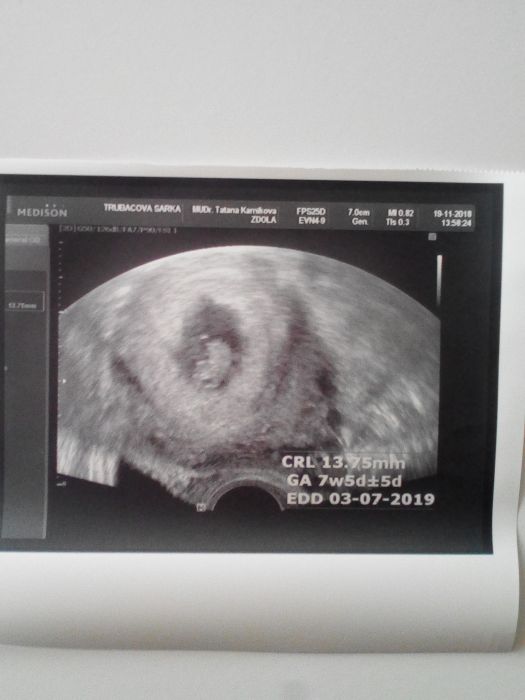

Ahoj holky, dnes jsem byla na první kontrole, vše je v pořádku, srdíčko krásně tluče a jsme o dva dny starší. Dnes tedy 7+5tt a TP vychází zatím na 3.7.2019 Mám velkou radost, že je vše jak má být a doufám, že to tak zůstane